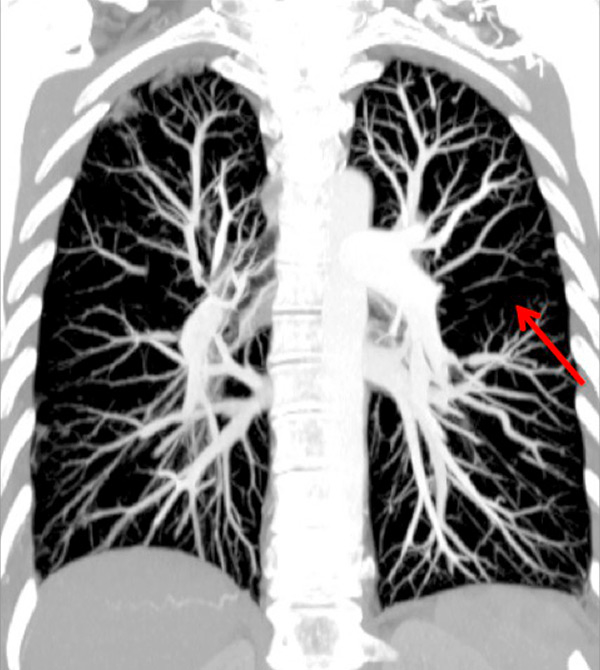

Figure 3

Chronic thromboembolic pulmonary hypertension (CTEPH). Segmental occlusions of pulmonary arteries (arrow) in the pulmonary angiography (A) are clearly visible on the CT angiography (B), with normal lung (C), and responsible for triangular perfusion defects (arrows) on the perfusion maps (D) confirmed by the ventilation-perfusion scintigraphy (E–F).